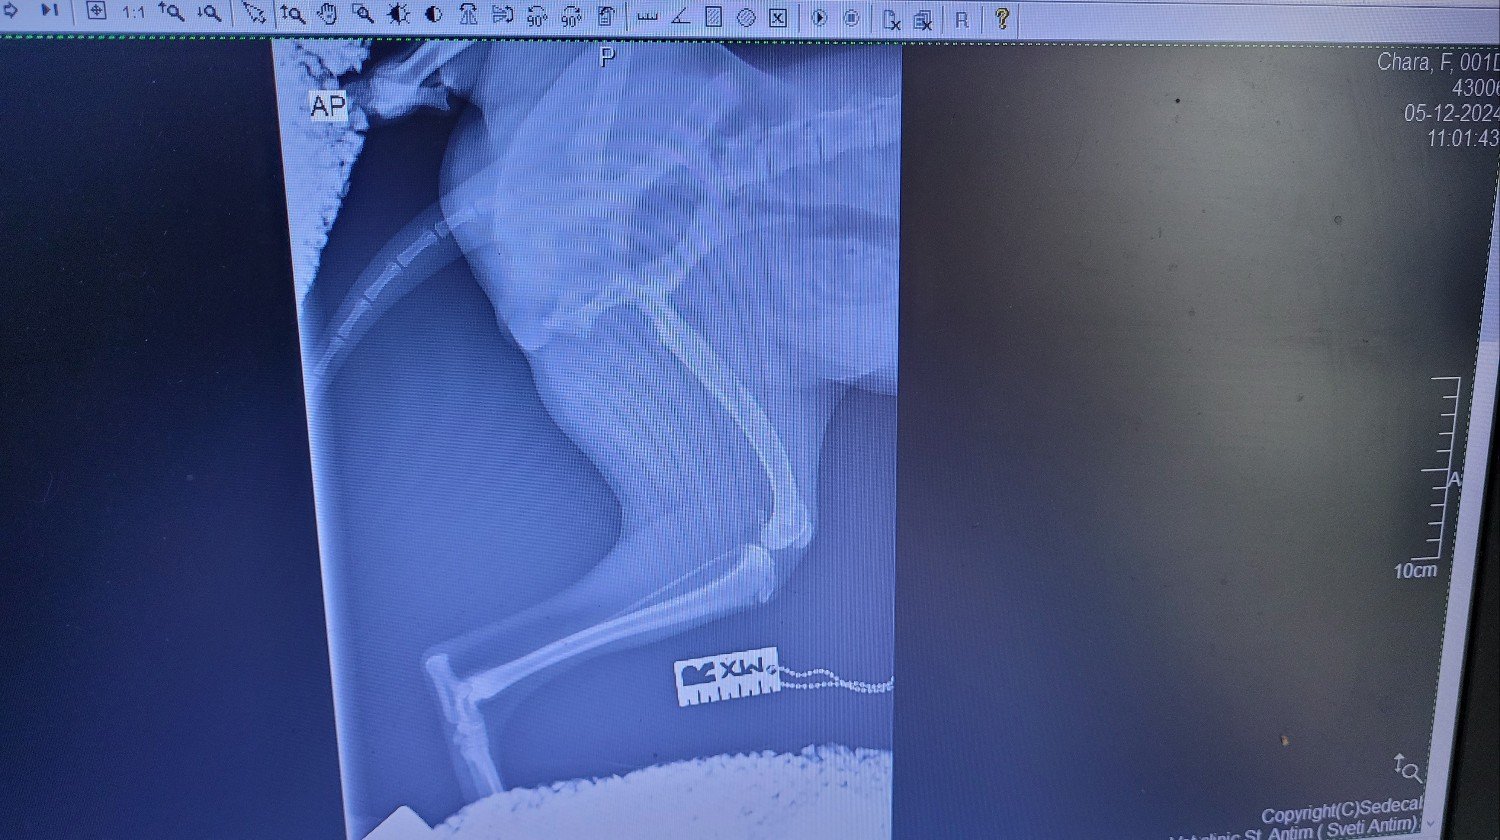

Ora è con noi da 3 mesi e oggi dovevamo fare una radiografia alle zampe e alla colonna vertebrale, poiché a volte zoppica leggermente con la zampa posteriore sinistra e mostra lievi segni di dolore.

È emerso che all'età di 1 o 2 mesi aveva una frattura alla zampa posteriore superiore che è guarita in modo non ottimale senza alcun trattamento. Di conseguenza, l'osso è un po' più corto e un po' curvo e il tendine esterno del ginocchio è allentato, per cui la sua rotula va verso l'interno della gamba. Questa situazione deve essere corretta con un intervento chirurgico, poiché il cane è ancora molto giovane e diventerà un handycapped molto presto nella sua vita. Al momento ha circa 8 mesi.

Non posso caricare molto qui, ma potete controllare il mio account TikTok Shushka1781 per vedere altre cose di Chara e Kalina-Bubka. Cercherò di caricare le radiografie in modo che possiate vederle.